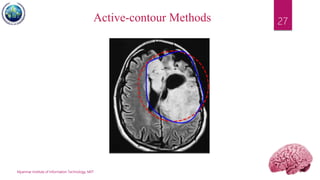

Active-Contour Methods

 Uses of energy forces and constraints for

segregation of the pixels of interest from the

image.

 Snakes: Active contour models. Kass, M.; Witkin,

A.; Terzopoulos, D. International Journal of

Computer Vision 1 (4): 321 (1988).

DOI:10.1007/BF00133570

 A snake is an energy minimizing, deformable

spline influenced by constraint and image forces

that pull it towards object contours and internal

forces that resist deformation.

27Active-contour Methods